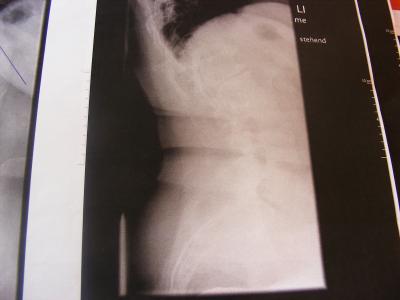

Nun habe ich konkrete neue und hoffentlich dann auch richtige Zahlen (ich kann auch nur die Zahlen angeben - welche ich von den jeweiligen "Orthopäden" bekomme) vom Grad der Krümmungen - ich hatte zu dem Zeitpunkt als ich mich angemeldet habe einen anderen Arzt mit dem ich nicht zufrieden war (was ich ja hier häufiger gelesen habe) und habe gewechselt, von dem Orthopäden hatte ich die Angaben in meiner Anmeldung, dann kam Orthopäde Nr.2 welcher mich gern auf der Schlachtbank gesehen hätte - heute nun Orthopäde Nr. 3 und bekam diese Angaben: Krümmung oben 63° Krümmung unten 56° dazu eine schwere Arthrose in der linken Schulter welche dort die starken Schmerzen verursacht! Ein Korrekturkorsett ist nicht mehr machbar, soll mit KG nach Schroth anfangen für die Krümmung BWS, jetzt habe ich erst einmal KG für die Arthrose in der Schulter bekommen, in der LWS hat sich die WS von selbst angefangen zu versteifen, daher auch die Aussage das ich kein Korsett mehr bekommen kann! Ich werd die Bilder mal abfotografieren und dann kann sich jeder mal selbst ein Bild davon machen!

So hier noch zwei Bilder....

Ich würde dir dennoch die Meinung eines Skoliose-Spezialisten empfehlen, der erstens die Korsettfrage klären kann und zweitens auch mal ordentliche Bilder von der Wirbelsäule macht, deine Bilder sind leider Teilaufnahmen.